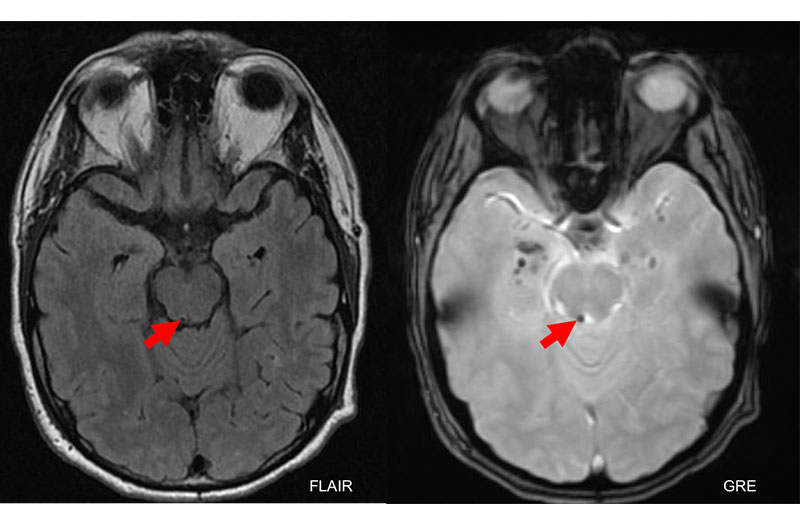

Bệnh nhân cũng có thể cần chụp CT Scan hoặc MRI sọ não hốc mắt để loại trừ khối u chèn ép hốc mắt, sọ não hoặc những bất thường tại não gây tăng áp nội sọ.

Trong quá trình thăm khám bác sĩ có thể phát hiện các liệt vận nhãn kín đáo gây ra triệu chứng cơ năng nhưng không có triệu chứng thực thể. Xác định nguyên nhân gây nên tình trạng này bằng chụp CT cắt lớp hoặc chụp MRI. Các phương pháp điều trị bệnh liệt dây thần kinh số IV hiện đang được áp dụng gồm: